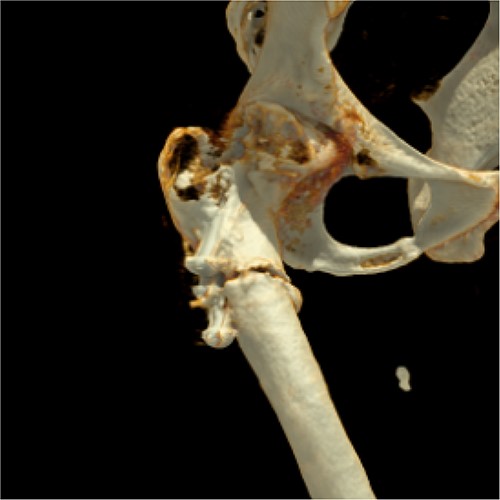

Two months later, the patient was represented to the emergency department after stumbling with progressive pain being conservatively treated due to bland diagnostics. Despite the good progress as seen in follow ups exampled in Fig. 1(B), the patient presented after another two months with atraumatic intense immobilizing pain of the right hip. Radiological diagnosis revealed a periosteosynthetic femoral shaft fracture as seen in Figs 1(C) and 2. The indication for the need of a TEP was given.

Three-dimensional reconstruction of computer tomography shows the patient’s periosteosynthetic fracture.